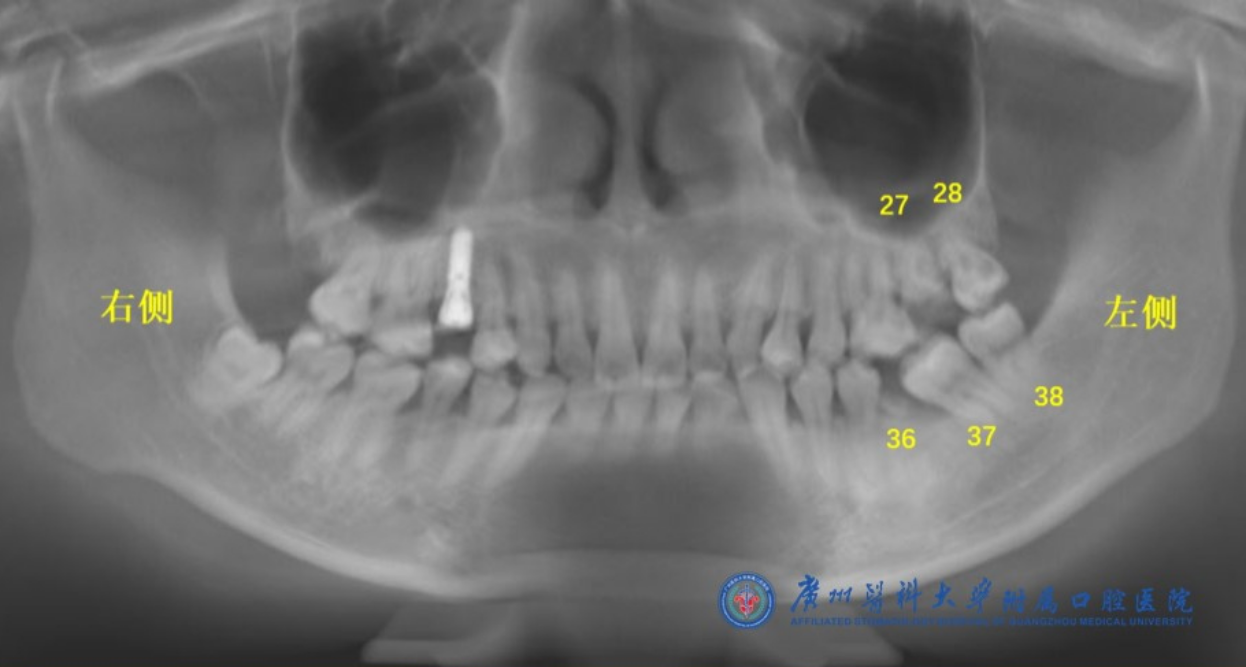

据周丽斌介绍,陈女士的左侧上下颌一共烂了3颗大牙(编号27、28、36),还有2颗严重倾斜的牙齿(编号37、38)(如图1所示)。按照经典的种植修复方案,这5颗牙齿都需要拔掉,然后再种植3颗牙齿(编号27处1颗,编号36和37处2颗)。

陈女士的三颗烂牙(编号27、28、36)和两颗倾斜牙齿(编号37、38)